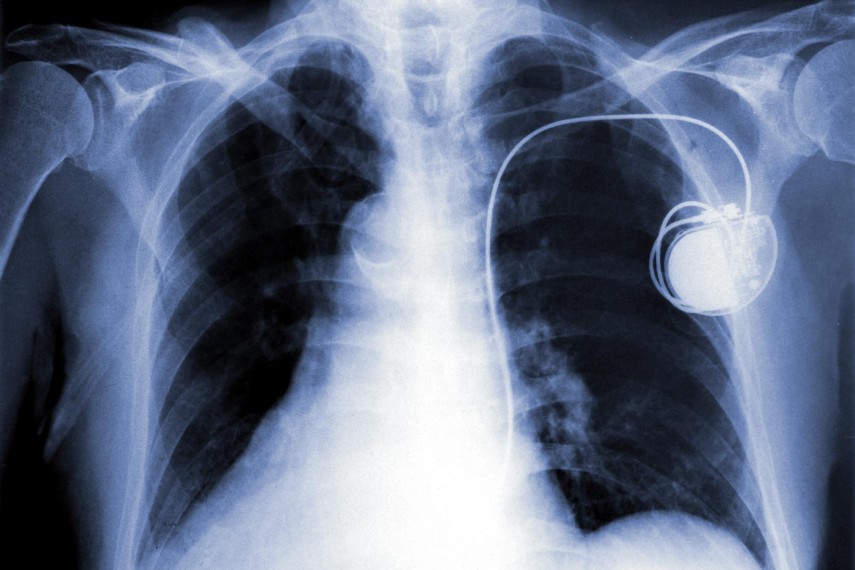

Személyre szabott pacemakert kapott egy páciens a Pécsi Tudományegyetem Klinikai Központ (PTE KK) Szívgyógyászati Klinikáján 2025 októberében.

Az aranybevonatú pacemaker beültetésére egy különleges eset kapcsán volt szükség: a páciens a hagyományos, titántartalmú generátorral szemben túlérzékenységi reakciót mutatott. A titánérzékenység egy rendkívül ritka állapot, amelynek kapcsán a szervezet allergiás reakcióval reagál a beültetett eszközzel szemben.

A pacemaker-generátort a beteg alapbetegségéhez igazodva, egyedi tervezést és részletes kivizsgálást követően készítették el a szakemberek. Ilyen típusú eszköz kereskedelmi forgalomban nem elérhető; minden esetben a beteg kórtörténetének alapos elemzése alapján gyártják és ültetik be. A speciális aranybevonat célja, hogy megelőzze az esetleges allergiás reakciót a beültetett készülékkel szemben. A nemzetközi szakirodalomban is mindössze néhány, hasonló jellegű beavatkozásról számolnak be; hazánkban első alkalommal került sor ilyen eszköz beültetésére.